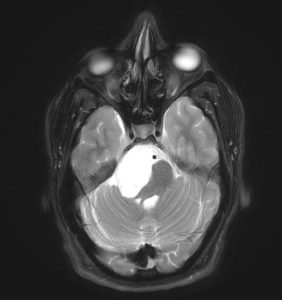

Η μετεγχειρητική αξονική τομογραφία εγκεφάλου δείχνει πλήρη αφαίρεση της βλάβης. Η ιστολογική εξέταση ανέδειξε επιδερμοειδή κύστη (Epidermoid Cyst, WHO Grade I)